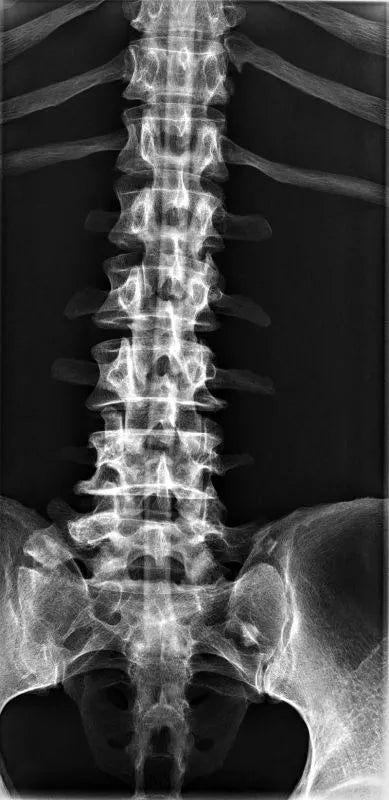

The whole-body X-ray phantom serves for practical training in projection radiography as well as in positioning and positioning techniques. It enables the production of realistic X-ray images under training conditions and depicts anatomical structures in their natural size.

The phantom contains a natural human skeleton. Additionally, the outlines of the larynx, lungs, heart, and kidneys are integrated, appearing as shadows on the X-ray images. This allows for the creation of images that accurately reflect the conditions found in patients. The use of a real skeleton enables the identification of bony landmarks that are not visible in plastic models.

The joints are mounted with full mobility, allowing positioning in common radiological standard positions, including special positions such as the frog position and pronation and supination of the forearm. The arms can be raised, so the phantom can also be used for bone examinations in CT scans. Particular attention was paid during assembly to the realistic representation of the joint spaces.

Each phantom is a handcrafted, unique piece. Variations in size, design, and appearance are possible. Depending on the model, pathological findings may be present. The revised design was developed in collaboration with a German training institution for medical-technical radiology assistants and meets the requirements of modern training concepts.